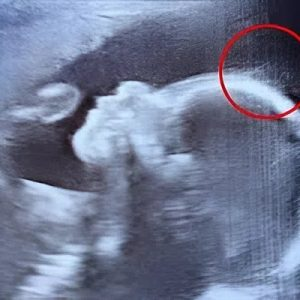

When 29-year-old Emily Foster from Kent, England, walked into the hospital for her 20-week pregnancy scan, she expected the usual routine: a grainy image, a few measurements, and maybe a glimpse of tiny toes. But what unfolded on the screen made everyone stop in their tracks.